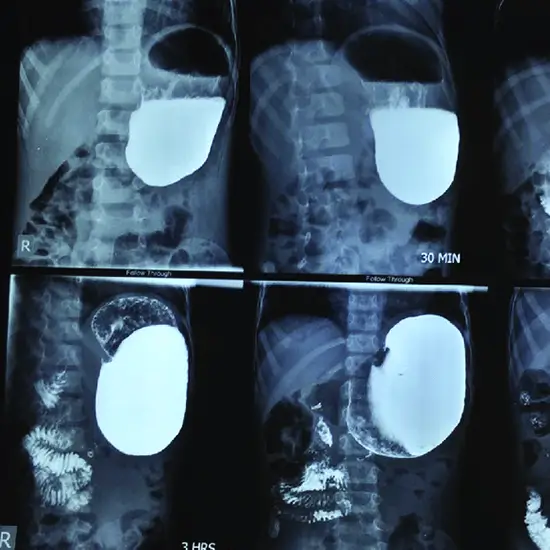

X-Ray Barium Meal Complete

A barium meal is a diagnostic procedure that uses X-ray imaging to detect abnormalities in the stomach, and small intestine.

The barium meal examination is a standard procedure done to assist in diagnosing a variety of digestive system diseases and problems. Constrictions, hernias, blockages or masses in the esophagus or stomach, and inflammatory conditions or other intestines disorders are examples of these conditions.